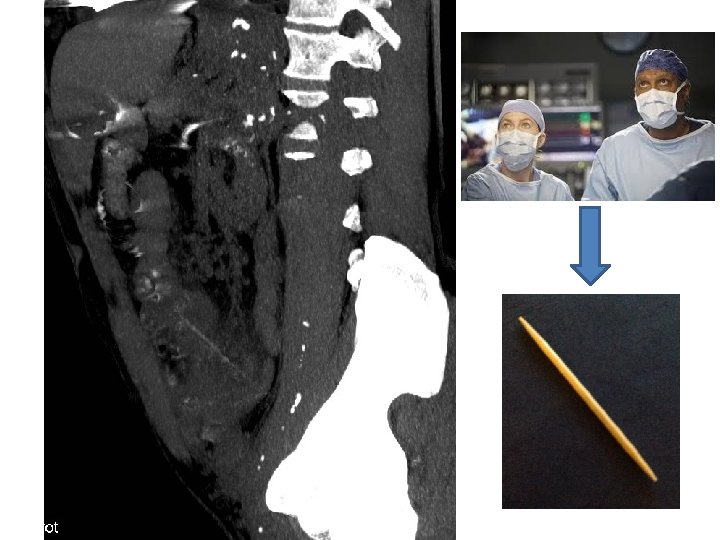

Les perforations du grêle sur corps étranger • Sièges de perforation des corps étrangers – Œsophage – Iléal ou iléocaecale – Rectosigmoïde • Type de corps étrangers: – Arêtes de poissons etc…

Peut on identifier le corps étranger? • Devenir des corps étranger ingérés: – 80 -90% passent spontanément, – 10 à 20% nécessitent des manœuvres non chirurgicales d’extraction et – moins d’ 1% le recours à la chirurgie.

Peut on identifier le corps étranger? • Les corps étrangers: – Sont le plus souvent radio-opaques: pièces, piles, aiguilles, épingles – Les cartilages, os, arêtes, morceaux de plastique, parfois verre ou alliage n’étant pas toujours radioopaques – Alimentaires sont le plus souvent radiotransparents.

« Un petit dernier… »

« Un petit dernier… » Abcès hépatique sur perforation du 2ème duodénum par une arête de poisson (fête du hareng à Dieppe)